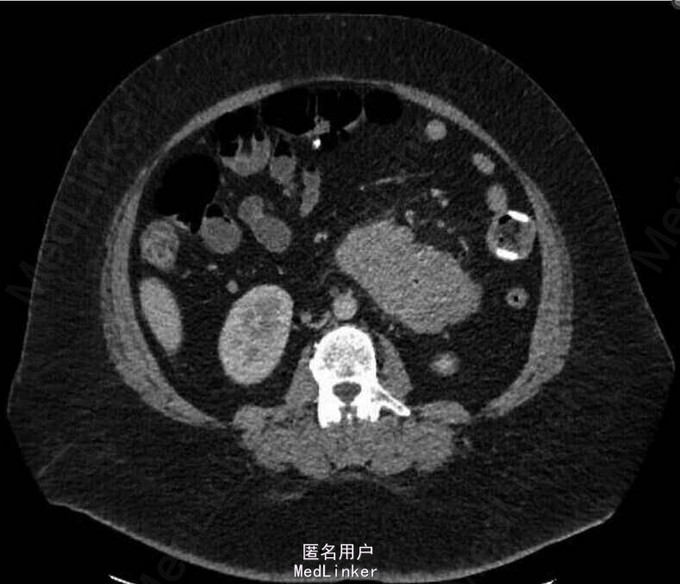

查体:发热(患者诉进行性加重,具体不详),心动过速,腹部稍膨隆。辅助检查:实验室检查提示白细胞增高(22×109/),CRP(359 mg/dl),腹平片提示胃十二指肠以及近段空肠扩张。CT检查提示胃束带移位,近段空肠梗阻,胃部出现扩张。

诊断:急性肠梗阻处理:迅速予以补液以及使用广谱抗生素。情况稳定后予以行腹腔镜下探查,证实胃束带确实有移位,而且近段的空肠出现了急性小肠梗阻,予以摘除胃束带。